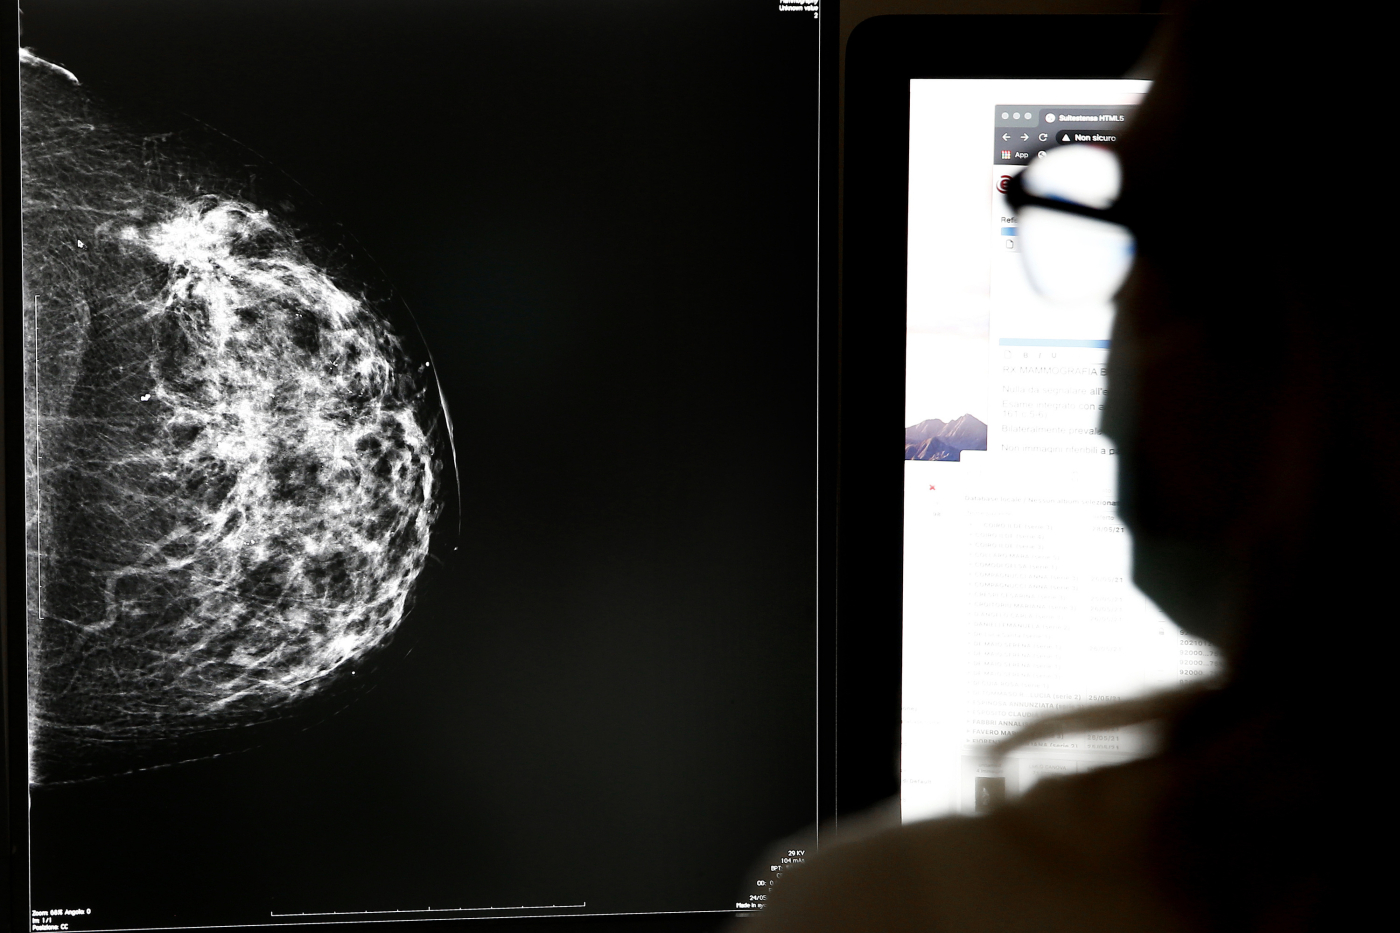

Il programma di “cribado” (screening) del cancro al seno è uno dei principali strumenti di prevenzione del sistema sanitario spagnolo. Ogni due anni, le donne tra i 50 e i 69 anni vengono invitate a sottoporsi a una mammografia gratuita. Se l’esame mostra segni sospetti, la paziente deve essere contattata entro poche settimane per ulteriori indagini.

Ma in Andalusia — secondo quanto emerso — questa catena di comunicazione si è spezzata. Migliaia di referti non sarebbero mai stati segnalati, lasciando molte donne senza diagnosi tempestiva. “È un fallimento del sistema”, ha dichiarato un radiologo dell’ospedale Virgen del Rocío di Siviglia, epicentro della crisi. “La carenza di personale e l’eccesso di burocrazia hanno fatto saltare i protocolli”.